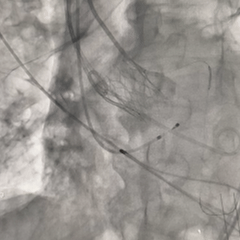

重新调整后重新定位

考虑第一次释放时瓣膜位置偏深,第二次瓣膜定位调整至瓣架底端约为瓣上4-5mm左右

第二次释放至全展开位

瓣膜释放过程中猪尾导管上移,瓣架轻微下移至瓣上2mm左右

全展开位造影评估

瓣架形态可,无窦侧深度约瓣上2mm,小弯侧深度接近零位,瓣架整体贴靠左窦侧,右冠显影正常,左冠显影尚可,可见少量瓣周漏